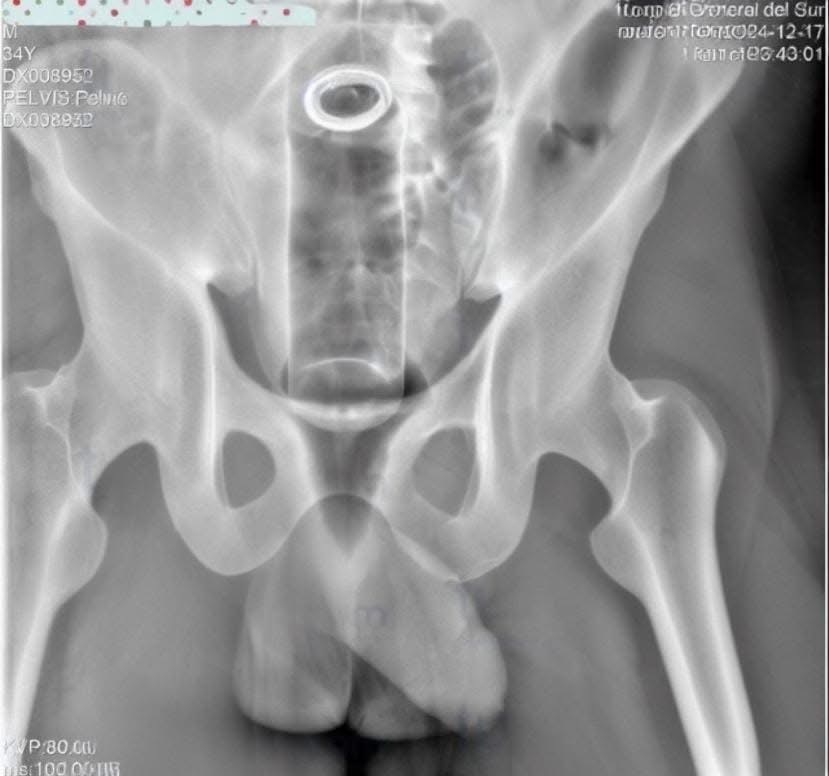

Choluteca- Un hombre de 34 años fue ingresado de emergencia al Hospital General del Sur en Choluteca tras introducirse un desodorante en el recto, según informaron las autoridades médicas.

De acuerdo con Nehemías Córdova, portavoz del hospital, el hombre presentaba un objeto extraño alojado en el conducto rectal.

“Se introdujo una barra de desodorante, pero no se sabe si fue intencional o un accidente”, declaró a medios locales.

El equipo médico realizó un procedimiento para extraer el bote, que había quedado atorado.